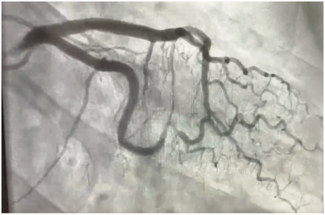

Pradnya Brijmohan Bhattad, MD; Luigi Pacifico, DO

A 54-year-old female presented with acute onset of typical substernal chest pain and was hemodynamically stable. A coronary angiogram (Figure 1/Videos 1-2, available on cathlabdigest.com) showed spontaneous coronary artery dissection (SCAD)...